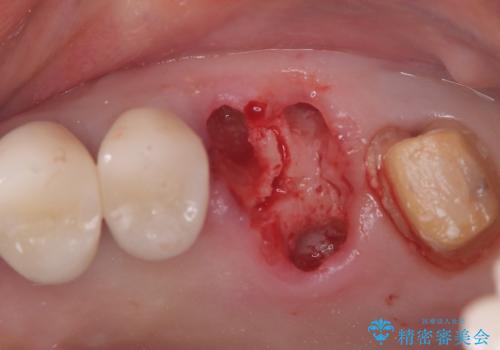

- 左上6番と7番の奥歯に、それぞれ遠心分岐部病変と頬側分岐部に10mmの深い歯周ポケットを認め、慢性的な炎症があります。再根管治療後も経過観察を続けましたが、病状の改善や歯周組織の付着が見られず、外科的歯内療法も選択肢にはありましたが、予後が不確実であること、そして患者様の負担を最小限に抑えたいというご意向を受け、抜歯即時埋入インプラントによる治療計画を立案しました。通常1年ほどかかる治療期間を大幅に短縮し、3ヶ月での機能回復を目指します。

今回のケースでは、特に難しいとされる奥歯の抜歯即時インプラントを適用しました。まず、炎症を起こしていた左上6番と7番を慎重に抜歯し、その直後にインプラントを埋入。この抜歯即時埋入により、歯を失ってからインプラントを埋入するまでの期間を省くことができ、骨の吸収を最小限に抑えられました。痛みや腫れもほとんどなく、患者様は「思ったより楽だった」と仰っていました。結果的に、通常であれば1年近く要する治療をわずか3ヶ月で完了。機能性と審美性を兼ね備えた新しい奥歯により、快適な食生活と笑顔を取り戻していただけました。